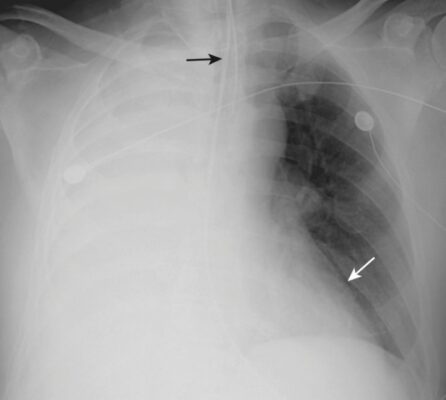

Xẹp phổi thùy giữa bên phải (xem Hình 1)

- Trên X quang thẳng:

- Có một đậm độ hình tam giác với đáy phủ bóng bờ với bờ tim phải và đỉnh của nó hướng về thành ngực bên.

- Rãnh liên thùy bé bị dịch chuyển xuống dưới.

- Trên phim X quang nghiêng:

- Có đậm độ hình tam giác với đáy hướng ra phía trước và đỉnh ở rốn phổi.

- Rãnh liên thùy bé có thể bị dịch chuyển xuống dưới và rãnh liên thùy lớn lên trên.